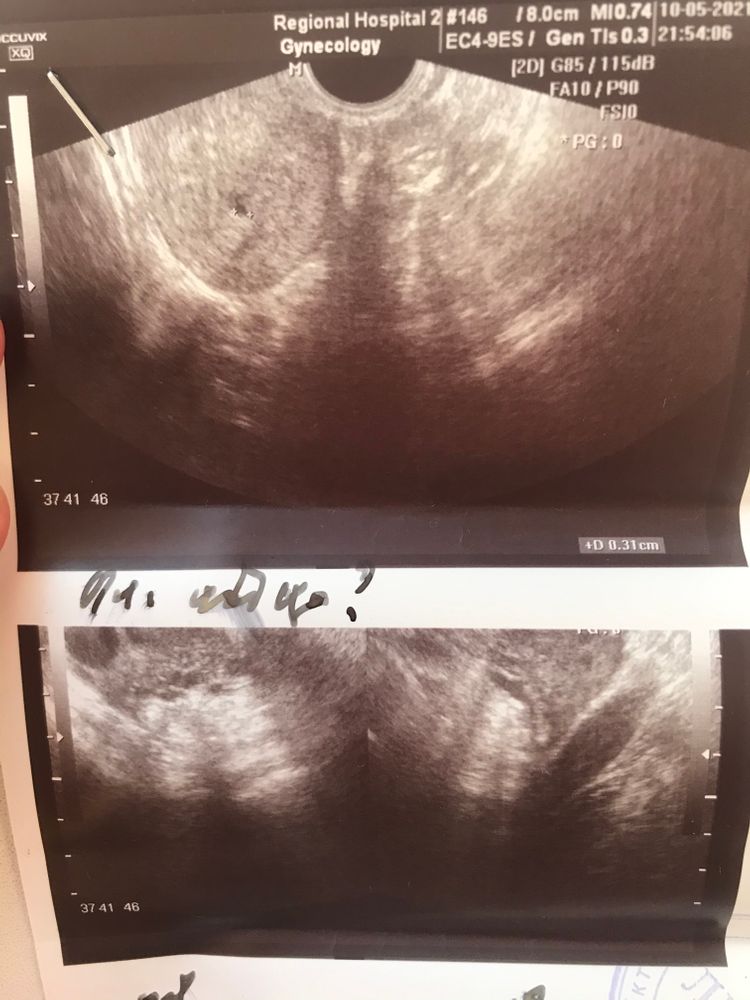

Пошла на узи 11 .05 - увидели пя -3 мм

Инна, а что это тогда в матке ?

моя онкогинеколог говорит , что не полип и не гематома

Даже если и хгч ошиблись, что маловероятно, то тест должен был быть положительным, а у вас отрицательный. Скорее всего ошибка узи, это не пя, может жёлтое тело

На УЗИ ошиблись,это не пя,не может быть беременности при отрицательном хгч